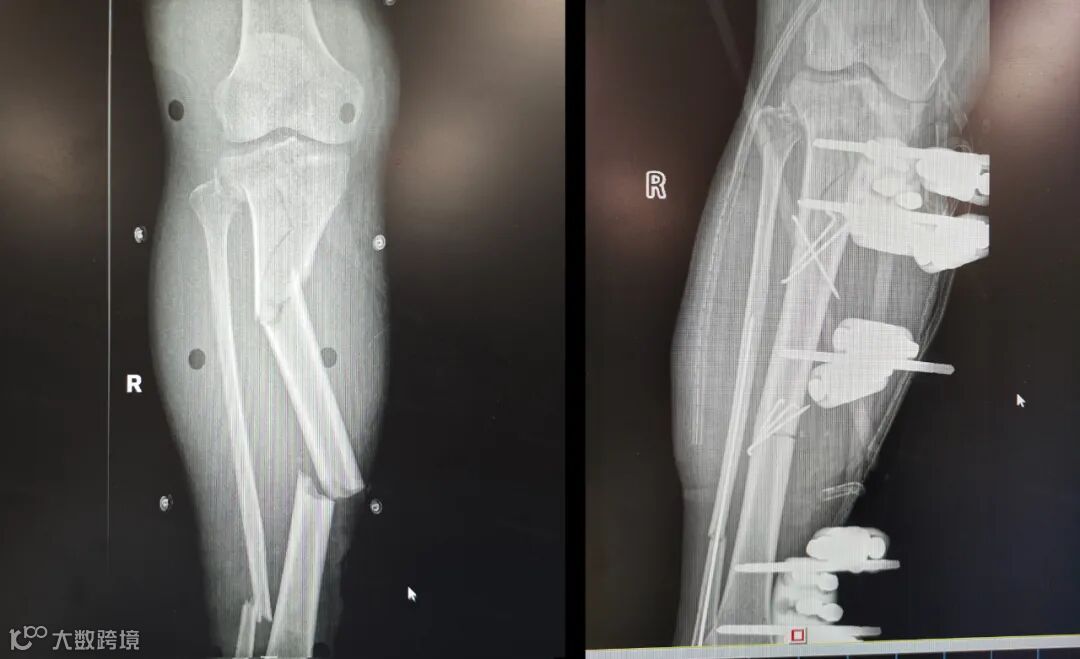

转院后,贾阿姨已处于休克状态,右脚出现花斑、淤黑,拍片显示右小腿断裂成三四截。值班医生迅速为患者完善血管彩超、血管 CTA 检查,确诊其小腿血管断裂。再不及时手术的话,贾阿姨的右脚就会坏死。

术中发现患者胫后动脉完全断裂,胫前动脉挫伤堵塞,医疗团队果断从患者对侧小腿取约 10 公分大隐静脉进行移植,成功建立远端血运。手术持续约5小时,涵盖血管移植、骨折固定、神经松解等复杂环节,术中输血900ml。

术前术后影像对比

图像经过处理